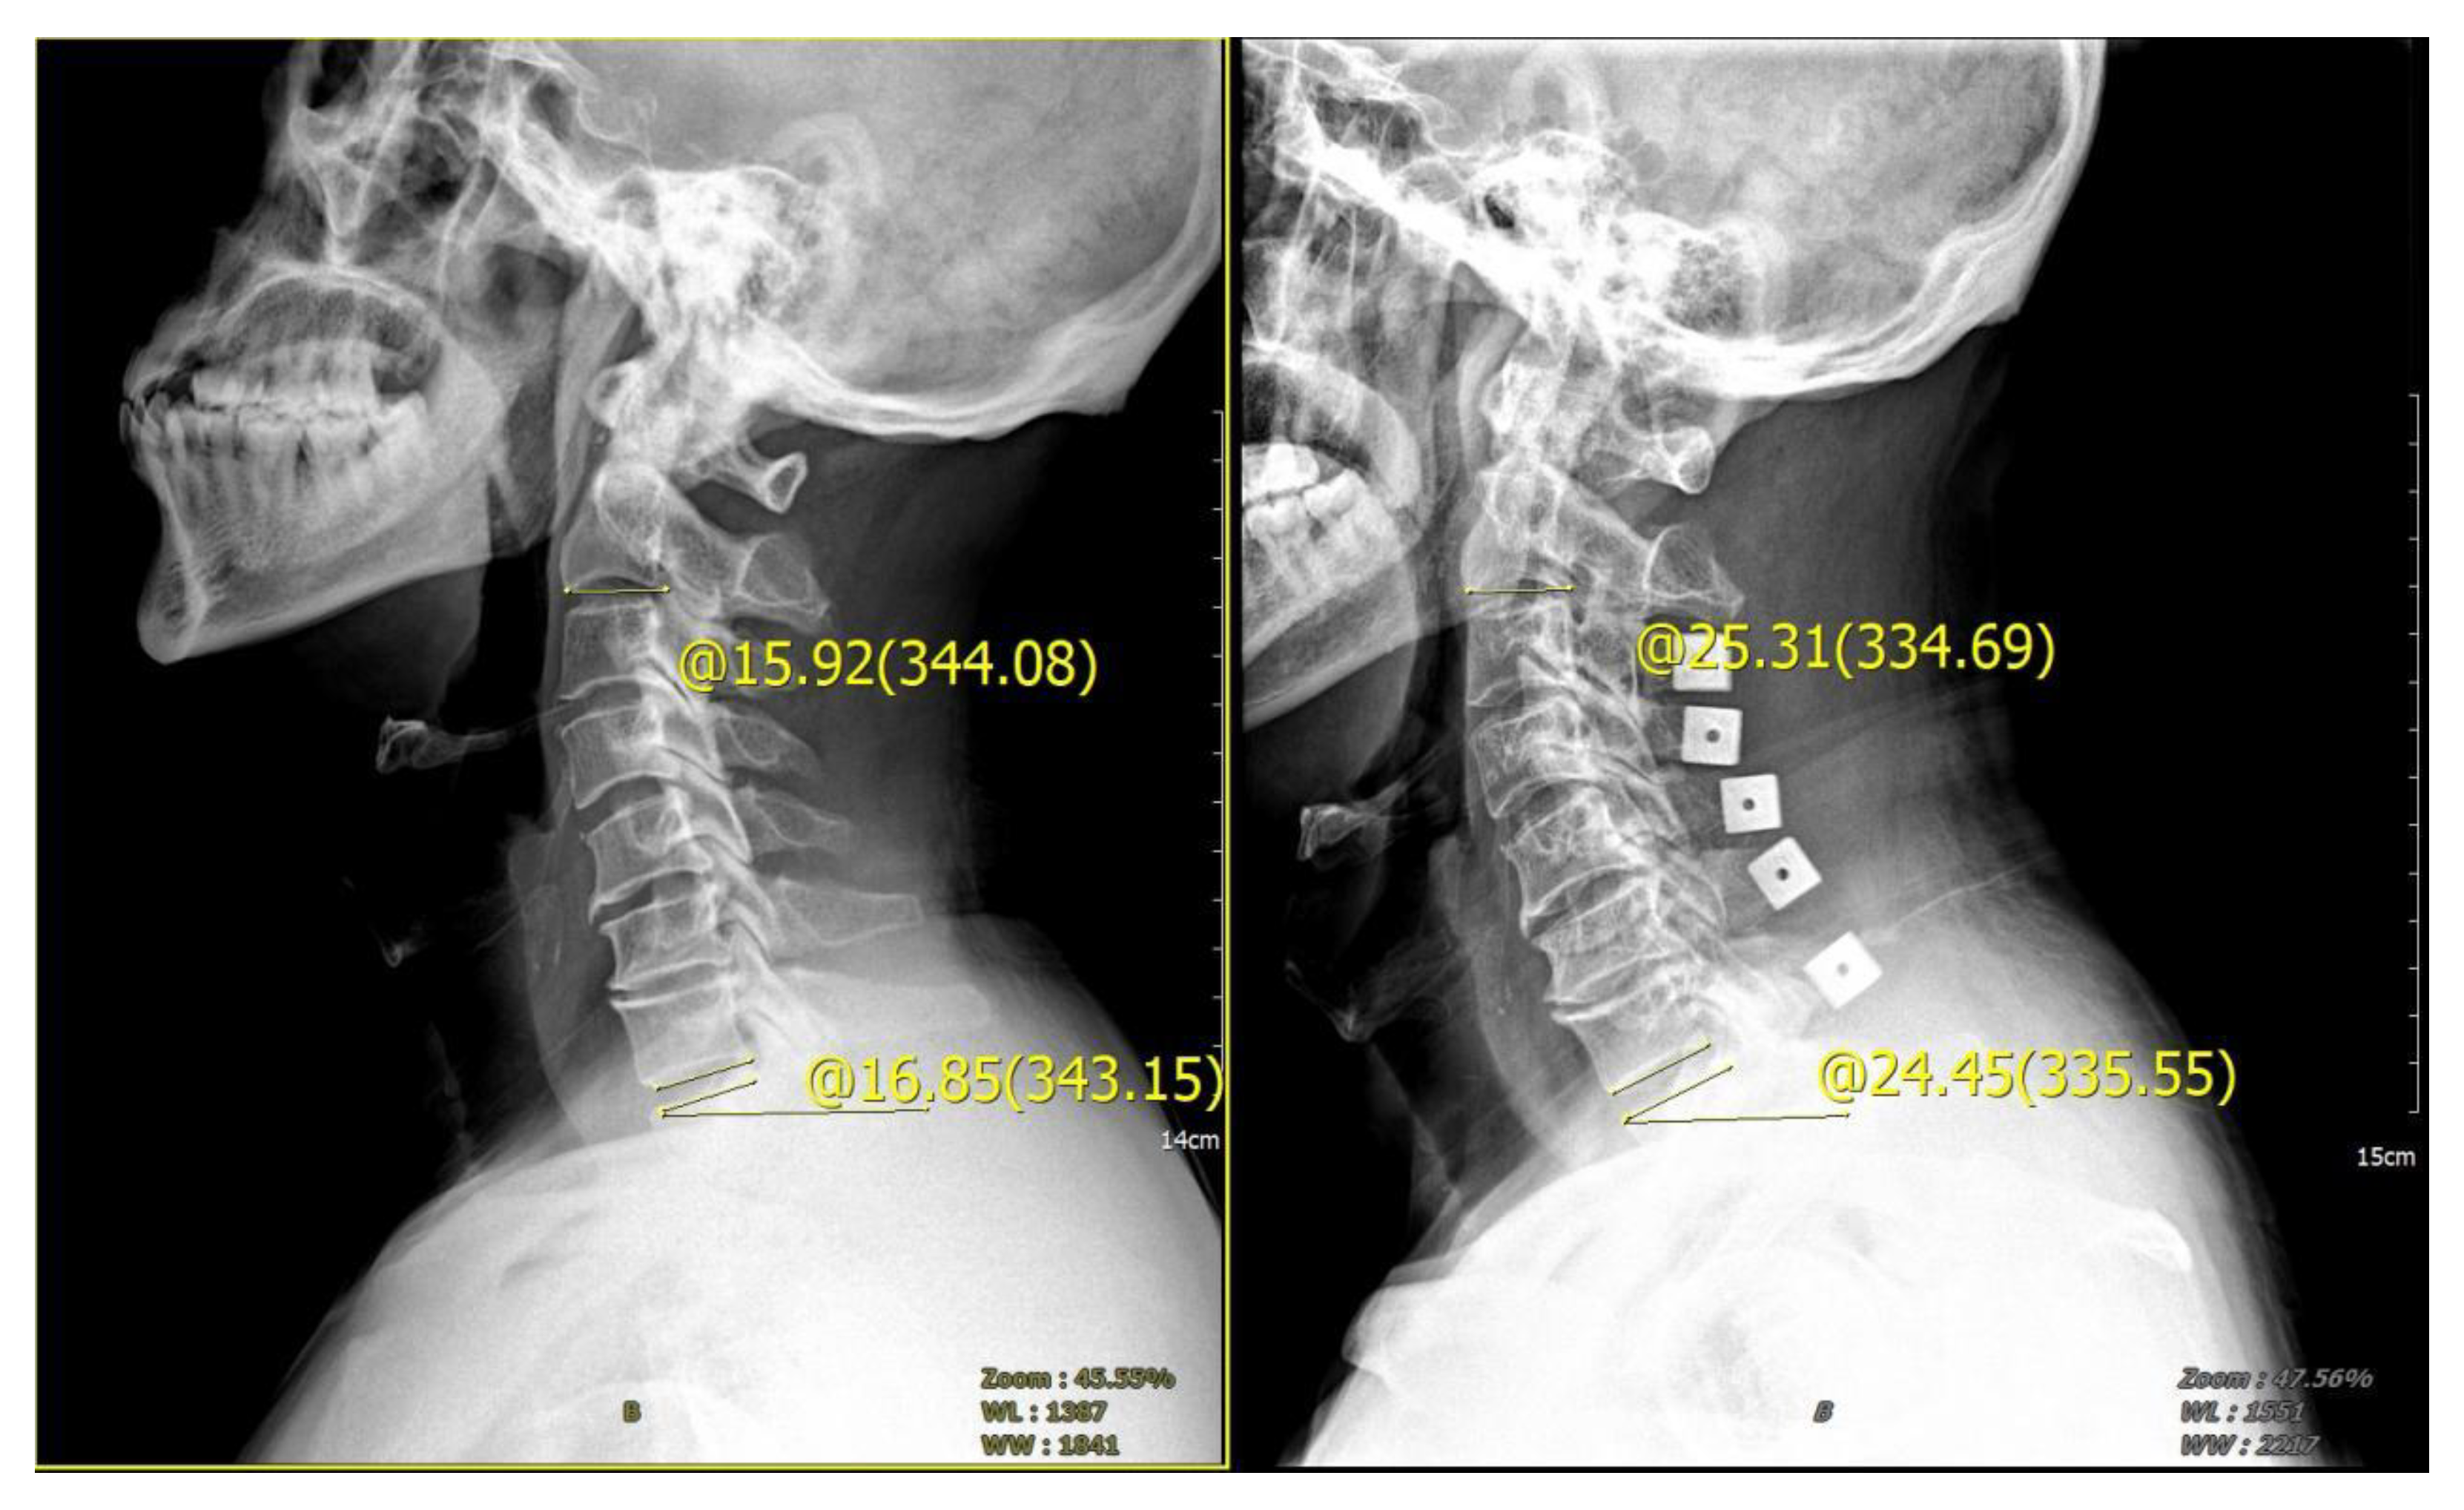

2.3. Measurement Standard